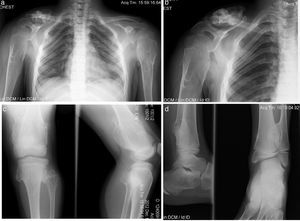

Paciente de sexo masculino de 8 años de edad con diagnóstico de hipotiroidismo subclínico desde los 8 meses hasta los 2.5 años, que se pudo normalizar. Se estableció el diagnóstico de OMH a los 2 años de edad, con lesiones en húmeros y muñecas. Su crecimiento ha sido satisfactorio, sin acortamiento de miembros inferiores, con peso y talla en el P50. Solo ha presentado disminución del arco de movimiento en muñecas y hombros y dolor ocasional en algunos movimientos articulares (fig. 4).

Caso 3 (III2). Paciente masculino de 8 años que presenta lesiones osteocartilaginosas con patrón heterogéneo de predominio radiolúcido en región clavicular derecha (a), exostosis en submetafisiarias en región proximal de húmero derecho (b), tercio distal de fémures (c), porciones proximal y distal de tibia y peroné (c, d). Hay deformidad con ensanchamiento medular en húmeros y fémures, principalmente. Las regiones fisiarias no están comprometidas.